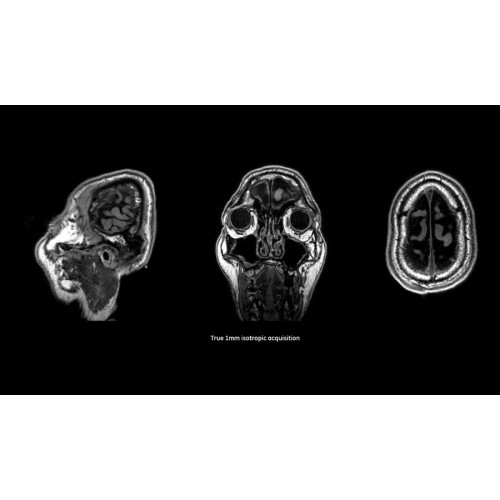

МРТ аппарат GE SIGNA Voyager 1.5T позволяет проводить полный спектр магнитно-резонансных исследований, включая нейровизуализацию, исследования опорно-двигательного аппарата, органов брюшной полости и малого таза, а также специализированные кардиологические программы.

МРТ-аппараты, Полуоткрытые аппараты МРТ, МРТ аппараты для животных